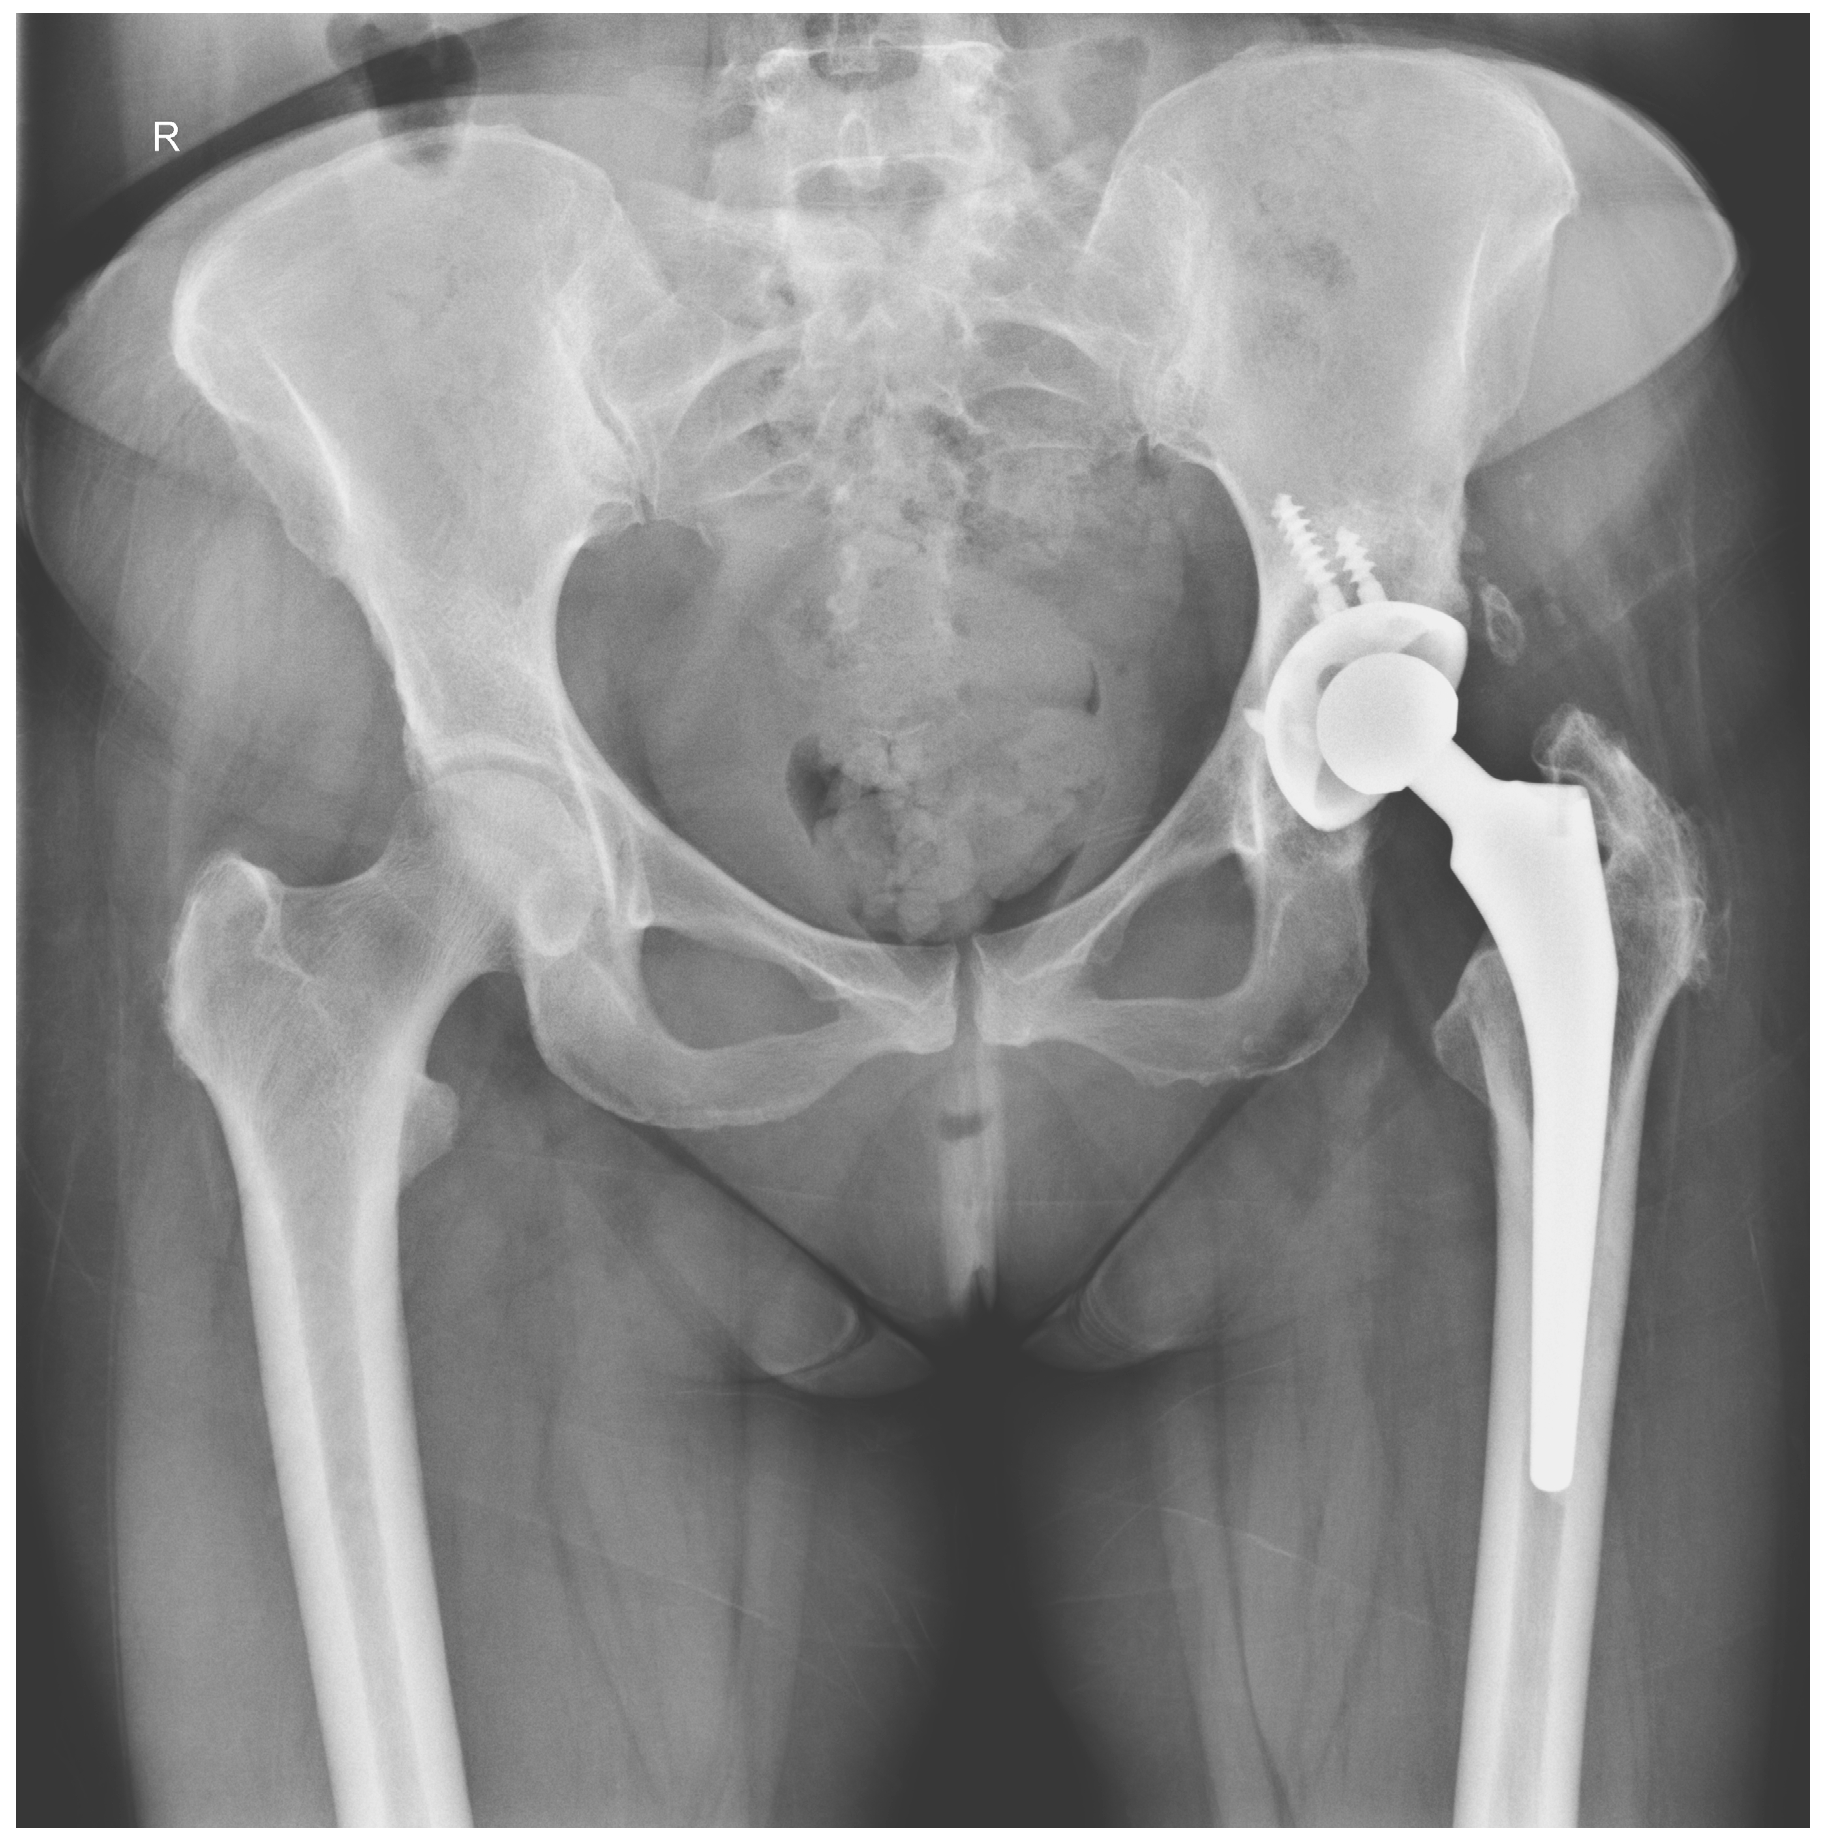

The Efficacy of Antibiotic-Loaded Calcium Sulfate Beads (Stimulan) in Patients with Hip Arthroplasty Infections

2.4. Surgical Procedure